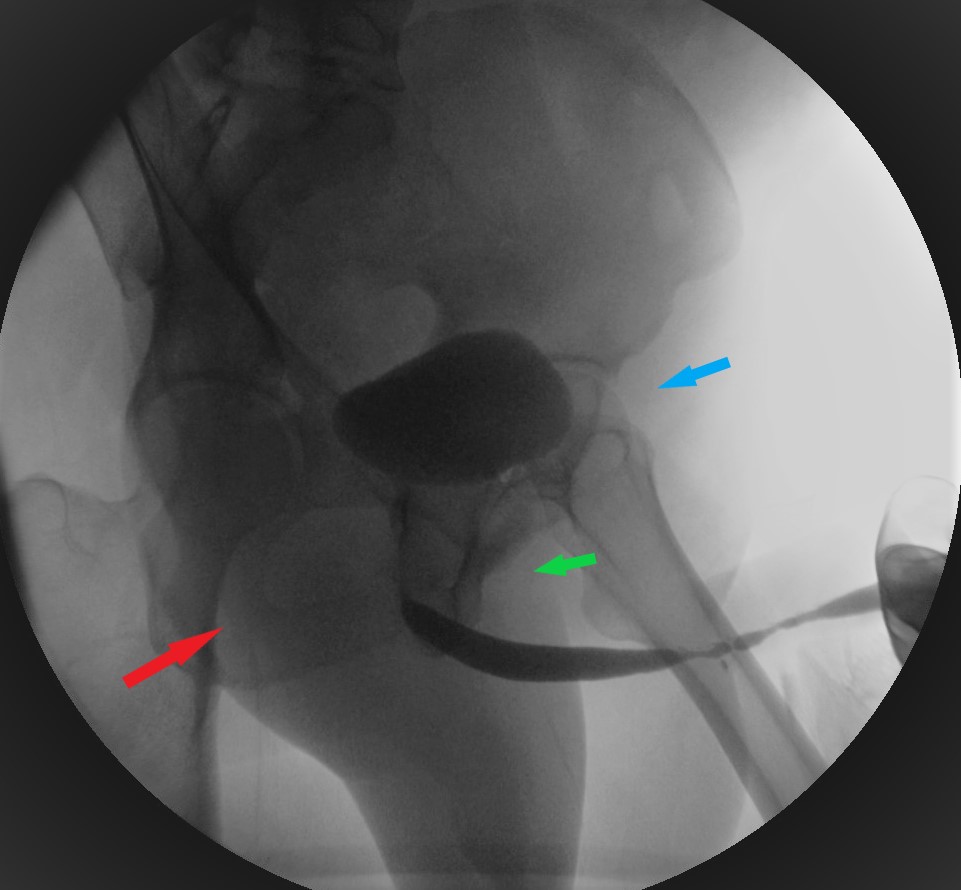

- La uretrocistografía retrógrada/miccional (UCG), es un examen dinámico que se realiza mediante la instilación uretral de contraste hidrosoluble bajo fluoroscopía y se recomienda que siempre sea hecha por el urólogo entrenado.20 Es el examen de elección para etapificación de las E/E. La UCG se encarga de definir la longitud, ubicación, severidad y número de las E/E. Además, da información sobre fístulas, duplicación uretral, falsa vía y el status del cuello vesical. El estudio completo consta de 2 fases: la fase retrógrada dibuja la uretra anterior y la fase miccional dibuja la uretra posterior, no siendo intercambiables, como se muestra en las imágenes. La fase retrógrada debe realizarse con el paciente en decúbito lateral con inclinación de 45°, permitiendo ver un orificio obturador “ocluido” en la imagen; con la cadera inferior flectada igualmente en 45° y la cadera superior extendida, y con el pene en estiramiento. (Fig 5). La fase miccional debe hacerse con la mesa en posición vertical y el paciente con deseo miccional, haciendo el registro en forma continua. (Fig. 6).

| Figura 5. Posicionamiento correcto en uretrocistografía retrógrada. Flecha celeste: flexión de cadera izquierda en 45°. Flecha roja: orificio obturador derecho se ve “abierto”. Flecha verde: orificio obturador izquierdo se ve “ocluido” debido al decúbito lateral izquierdo en 45°. |